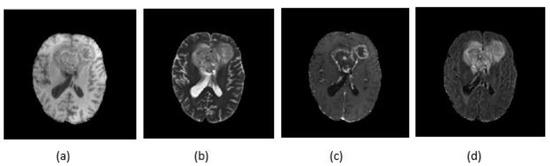

The proposed CNN architecture was applied on MRI images; these types of images can show different tissue contrasts across different pulse sequences, making it an adaptable imaging technique widely used to visualize regions of interest in the human brain. There are four MRI sequences available for every patient: T1-weighted (T1), T1-weighted and contrast-enhanced (T1c), T2-weighted (T2) and T2-weighted FLAIR (FLAIR) (Figure 3). Each one of these modalities contains information that signifies performance improvement.

Figure 3.

Different modalities of MRI images: (a) T1; (b) T2; (c) T1c; and (d) FLAIR.

In our study, since our objective concerned complete tumor segmentation, we used the FLAIR image because it detects the tumor with peritumoral edema and it facilitates the segmentation of the whole tumor.